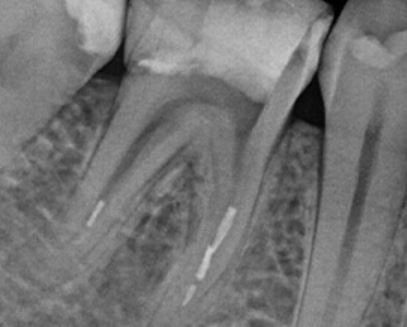

Le glide path désigne la préparation initiale du canal radiculaire avant la mise en forme finale. En pratique clinique, son obtention se manifeste par une sensation au bout des doigts comparable à la glisse sur un toboggan, menant directement et sans résistance jusqu'à l'apex.

Cette phase préparatoire est essentielle car elle facilite le passage des instruments mécanisés jusqu'à la longueur de travail désirée, en minimisant les contraintes excessives sur les instruments et les parois canalaires.

• Vérifier avec le localisateur d'apex et une radiographie de contrôle

• S'assurer de la perméabilité apicale (légère sensation de cran)